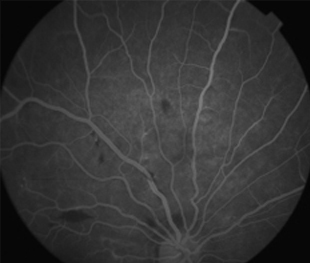

Angiografía OD

- Angiografía: teñido arterial, escape capilar, más tardíamente, no perfusion arteriolar y venular con teñido de las paredes vasculares y dilatación venosa.